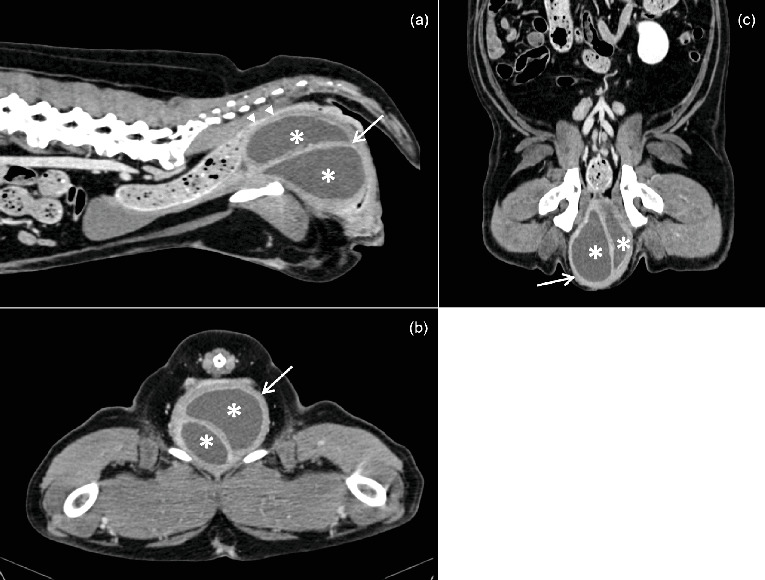

An 11-year-old neutered female Labrador was presented with dyschezia and dysuria associated with a large perineal mass that had been present for 2 years. Computed tomography (CT) revealed a large bilobed, cavitated mass localized ventrally to the rectum and dorsally to the urethra at the level of the vagina, with hypoattenuating contents and a contrast-enhancing peripheral wall. Surgical excision was performed and confirmed the cystic nature of the mass. Histopathological findings were compatible with a benign vaginal cyst, most likely originating from the Müllerian or paramesonephric ducts. The CT provided relevant information for surgical planning and enabled accurate assessment of the mass's location, extent, and relationship with adjacent structures.

摘要一位11岁的绝育拉布拉多犬,因出现2年的会阴大肿块而导致排尿困难。计算机断层扫描(CT)显示一个大的双叶状空洞肿块,位于直肠腹侧和阴道水平的尿道背侧,内容物低衰减,周围壁增强。手术切除后证实肿块为囊性。组织病理学检查结果符合良性阴道囊肿,最可能起源于勒氏管或肾旁管。CT为手术计划提供了相关信息,并能够准确评估肿块的位置、范围以及与邻近结构的关系。